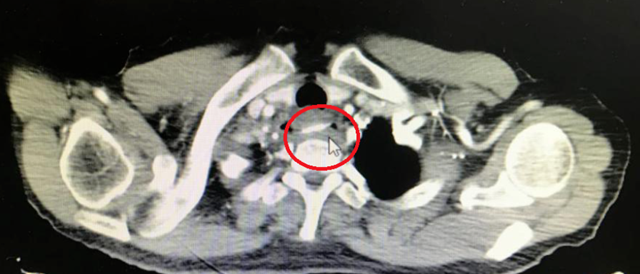

前天晚上7点,一位82岁的老奶奶被家人急匆匆地送到西南医科大学附属中医医院耳鼻咽喉科就诊,家人说中午家庭聚餐时,大家说说笑笑,不想老奶奶突然说骨头哽到喉咙里了,怎么也咯不出来,后面一吃东西咽喉下头就痛,家人想着可能一会儿就好了,先观察一下...